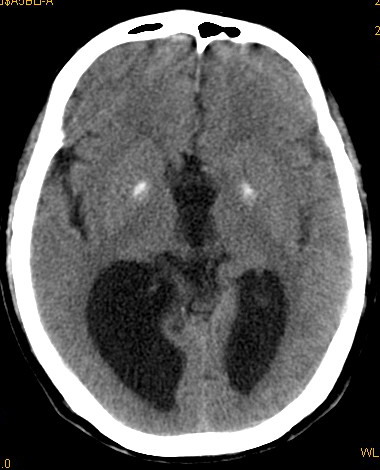

以下是引用卜一在2008-8-14 16:31:00的发言:[br]支持:巨脑回伴脑积水!另:胼胝体发育不良!

以下是引用同在2008-8-14 19:46:00的发言:[br]巨脑回伴积水,胼胝体发育不良.